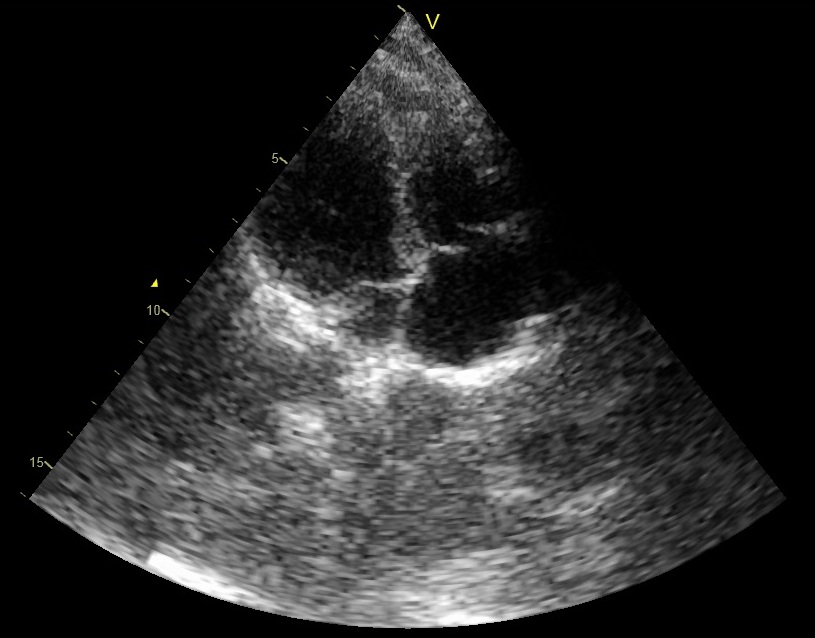

The resulting images, corresponding to two different frames, are shown in Figs. 7f (b) and (e). Although the images are not identical to those obtained by standard beamforming (Figs. 7f (a) and (d)), it can be easily seen that optimization, based on the assumption that the signal of interest is compressible, allows to reconstruct both strong reflectors and speckle. Table II reports corresponding values of NRMSE and SSIM. Although the quantitative values are reduced compared to those obtained in Sec. IV-B, important information, e.g. the thickness of the heart wall and the valves, as well as the speckle pattern, essential for tracking tools, are preserved.

To compare the proposed method with the previously developed optimization based approach, we solved (29) with OMP, while assuming strong reflectors in each direction . Resulting images, shown in Figs. 7f(c) and (f), depict the strong reflectors, observed in Fig. 7f(a) and (b), while the speckle is completely lost, degrading the overall image.

Using this set, beamforming in frequency was performed according to (16) and (20), yielding the DFT coefficients of the beamformed signal. In this setup the sampling rate remained unchanged, but frequency domain beamforming was performed at a low rate. In our experiments we computed DFT coefficients of the beamformed signal, using DFT coefficients of each one of the detected signals. This corresponds to real-valued samples used for beamforming in frequency. The number of samples required by demodulated processing rate is . Hence, beamforming in frequency is performed at a rate corresponding to of the demodulated processing rate. Images obtained by low-rate beamforming in frequency and standard time-domain beamforming are presented in Fig. 11. As can be readily seen, we are able to retain sufficient image quality despite the significant reduction in processing rate.